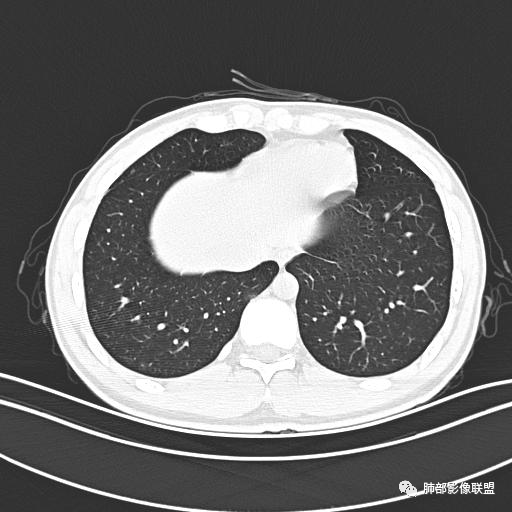

男,19岁

主  诉:发热、全身皮疹2天。

现病史:患者源于2天前受凉后出现发热,最高体温为38.5℃,且颜面部出现少量皮疹,无鼻塞、流涕、咳嗽、咳痰,未在意而未作特殊处理,次日全身皮疹逐渐增多至全身,伴轻度瘙痒,在当地卫生所给予抗病毒、抗感染治疗(具体用药不详)体温有所下降,但皮疹无明显消退,无腹痛、头痛,食欲无明显减退,为进一步诊治,遂于今日急来我院求治,患者目前精神尚可,体力正常,食欲正常,睡眠正常,体重无明显变化,大便正常,排尿正常。

小强:青年,发热,皮疹;双肺散在结节,周围磨玻璃,点晕征,疱疹病毒感染,鉴别荚膜组织胞浆菌,结核。 大雄:青年,急性起病,发热伴全身皮疹2天,抗病毒治疗体温有下降。双肺随机分布大小不等类圆结节,“点晕征”。考虑水痘-疱疹病毒(VZV)血播询问接触史,查体皮疹分布以及形态基本可诊断。 王开金江津中心医院呼吸科:青年男性,起病急,病程短,以发热,皮疹为首发症状,感染指标以单核细胞升高为主,胸部ct双肺多发结界,周围有晕,点晕表现,随机分布,同意於老师意见,水痘疱疹病毒血流感染累及肺。 王秀仙:双肺多发大小不等结节,周围有晕,边缘模糊,呈点晕征表现。青年,急性起病,发热伴全身皮疹2天,抗病毒治疗体温有下降。考虑疱疹病毒。鉴别荚膜组织胞浆菌。 傅昌瑜:19岁男性,发热、全身皮疹2天,单核细胞增高,双肺多发结节,结节边缘见边界不清磨玻璃影。点晕征+发热、全身皮疹+单核细胞增高——考虑水痘-带状疱疹病毒肺炎。 一切∮随缘:年轻男性,发热,皮疹两天,实验室,CRP,PCT增高,影像:双肺多发散在磨玻璃结节,边界欠清,大小不等,呈点晕征改变,以血管束周围分布为主,局部血管束略增粗,其它无明显改变,考虑:1:病毒性肺炎(水痘疱疹病毒?不知道皮肤有无改变)2:真菌(组织胞浆菌,血管侵袭性肺曲霉)3:GPA4:寄生虫(实验室没有看到嗜酸细胞增高) 赵山河:双肺散在结节,周围有晕,边缘模糊,呈点晕征表现。青年,急性起病,发热伴全身皮疹2天,抗病毒治疗体温有下降。考虑水痘—疱疹病毒感染。洪桥爱:青年男性,发热、皮疹2天,伴瘙痒,皮疹于面部首发,之后进展至全身,虽然没有对皮疹进行描述,但是从出疹时间及皮疹进展情况,伴瘙痒,应该就是个水痘患者;CT提示双肺随机分布结节影,部分结节伴有边界不清晕征,考虑水痘血播肺。 刘强:年轻男性,急性起病,皮疹,发热,抗感染治疗体温下降,说明有效。影像表现为散在点晕征,感染类疾病谱(疱疹病毒,真菌,结核),结合年龄,皮肤皮疹,考虑水痘-疱疹病毒性肺炎。 小兜:男性,19岁,发热皮疹两天,颜面部至全身,CRP,降钙素及单核增高。CT示双肺散在小结节,周围伴磨玻璃影,点晕征,考虑为水痘-带状疱疹病毒(varicella-zoster virus,VZV)肺炎 必有路:青年,皮疹+发热+“点晕征”→水痘-疱疹病毒(VZV) 许慧良:青年男性患者,发热、皮疹2天,体温最高38.5℃,第3天皮疹扩展至全身,伴瘙痒,胸部CT:双肺多发随机分布的小结节,结节周边见边界模糊的晕征,考虑水痘病毒感染流心明智:男,19,急性起病,发热伴全身皮疹2天。出疹顺序头→全身,抗病毒有效。胸部CT:两肺多发大小不等类圆形实性小结节影,随机分布,结节周围环绕GGO,边界模糊,呈点晕征。出疹特点是关键,未提示。考虑:血播病毒性肺炎,水痘-疱疹病毒?麻疹?鉴别荚膜组织胞浆菌、TB、血管炎、寄生虫等。 浪迹天涯:病灶多为5-10mm大小结节,结节周围可见磨玻璃样的晕环,常多发,可分布于肺内任何区域,考虑水痘—带状疱疹病肺炎如果短时间内有新的一个区域浸润,更加能说明,